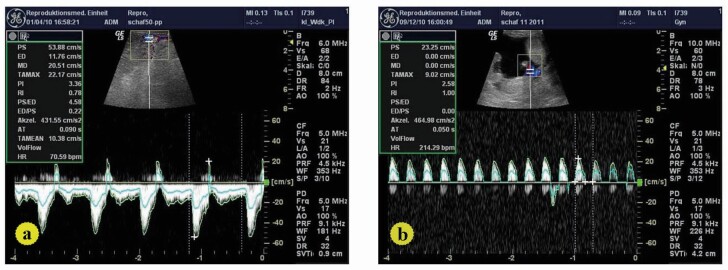

This study aimed to examine the efficacy of Doppler and B-mode sonography in evaluating the impact of maternal temperament on hemodynamic alterations in both the fetus and uterus during ovine gestation in addition to alteration of the angiogenic protein expression and fetal biometry. Twenty Ossimi ewes were divided into two groups, more reactive (MR: 12 sheep) and less reactive (LR: 8 sheep). Several endpoints were assessed every 2 weeks (wk) from breeding to wk 20 of pregnancy. Blood samples were taken to evaluate the expression of angiogenic proteins at parturition. The resistance (RI) and pulsatility (PI) indexes of the uterine (UtA) and fetal umbilical arteries (UMA) were measured. Biometry includes: diameter of amniotic vesicles (AVD), umbilicus (UMD), fetal thoracic diameter (FTD) and metacarpal length (MCL). The UtA-PI was higher in MR compared to LR ewes between 6-12 wks of gestation (P>0.01), while a tendency was recognized at wk 14 (P=0.054). The same was true for UtA-RI during the first 8 wk of pregnancy (P < 0.03) when MR and LR animals were compared. Similarly, UMA-RI was higher in fetuses of MR than LR ewes at wk 14 (P<0.0003) and 20 (P<0.02) of pregnancy. The differences in UMA-PI reached significance at wk 6, 8, 10, and 20 (P<0.0 -0.003). Furthermore, significant changes in fetal biometry were investigated. The expressions of VEGF, NOS3 and HIF 1α were increased in the less reactive sheep (P<0.001). In conclusion, the maternal temperaments affect the Doppler, B mode as well as the expressions of mRNAs for VEGF, NOS3 and HIF 1α genes at time of parturition.